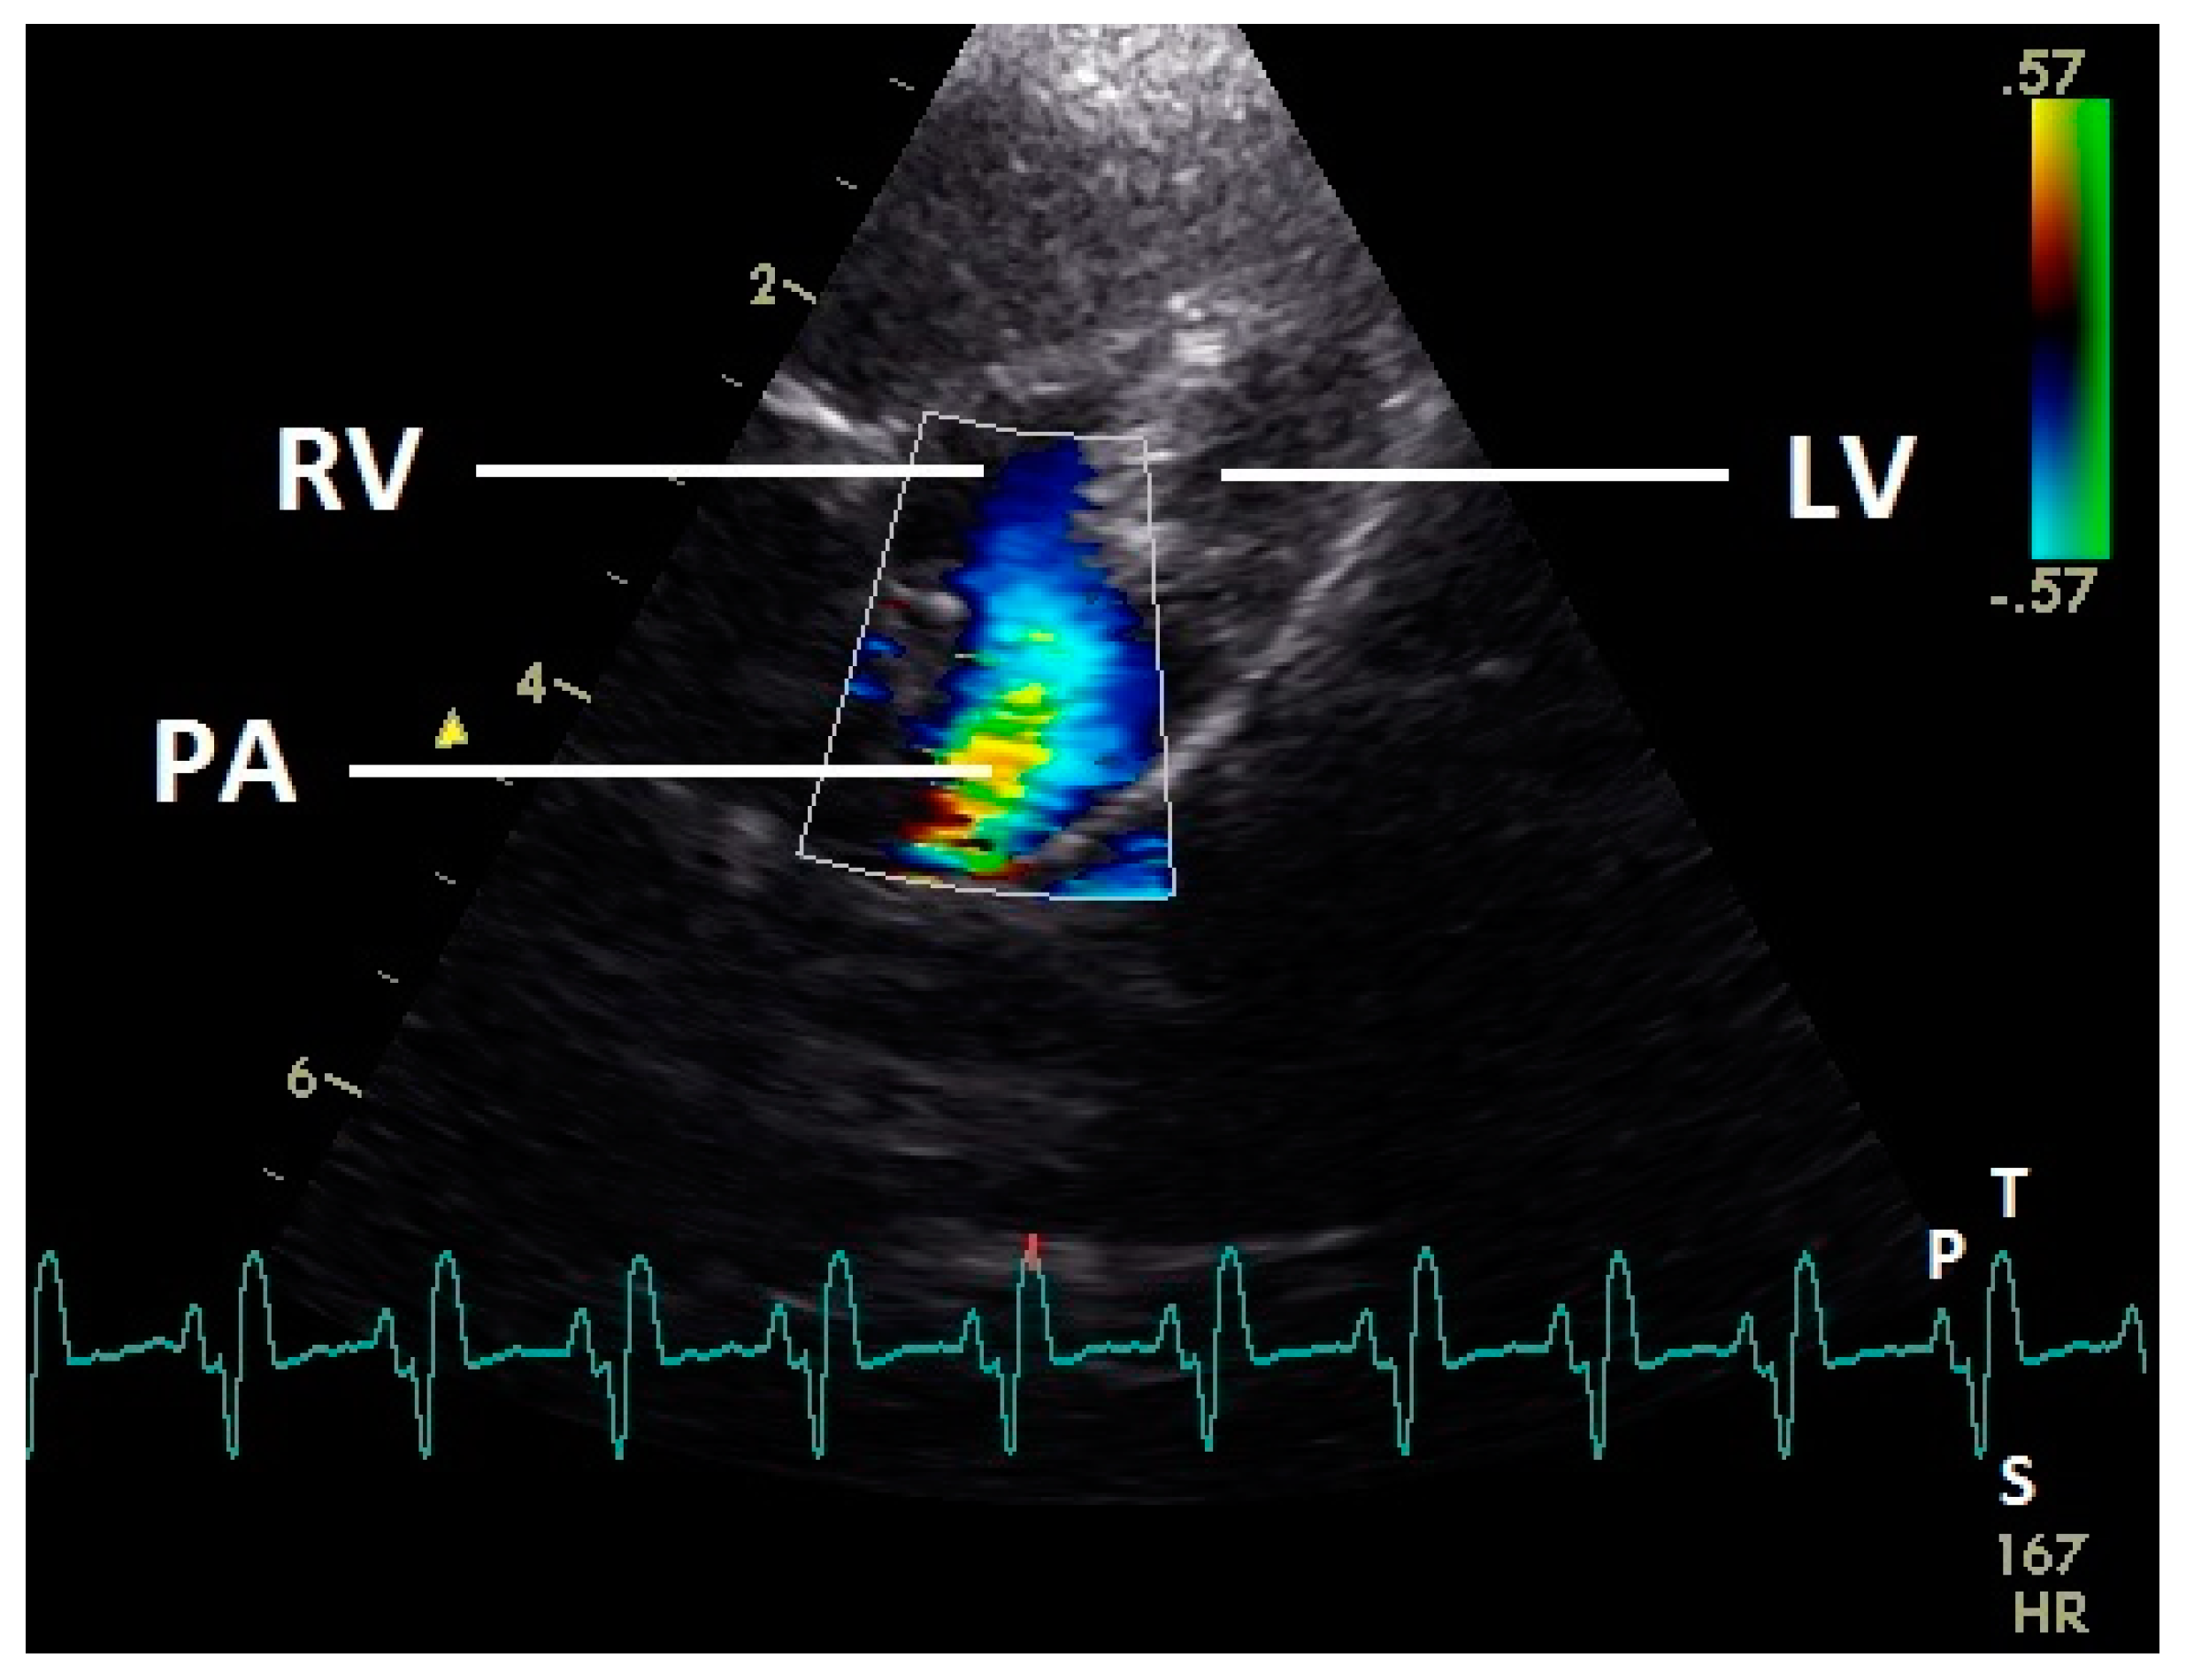

Figure 10.

Color Doppler image of the right ventricle in the systole. The blood ejection from the right ventricle in the pulmonary artery is visible (blue signal). The blue flow signal is aliased in the pulmonary artery (wrong direction: red instead of blue of the color Doppler signal in the pulmonary artery). LV: left ventricle; RV right ventricle; PA: pulmonary artery; HR: heart rate. Electrocardiogram: P: P wave, S: S wave, T: T wave. The color scale on the right of the image is calibrated in m s−1.